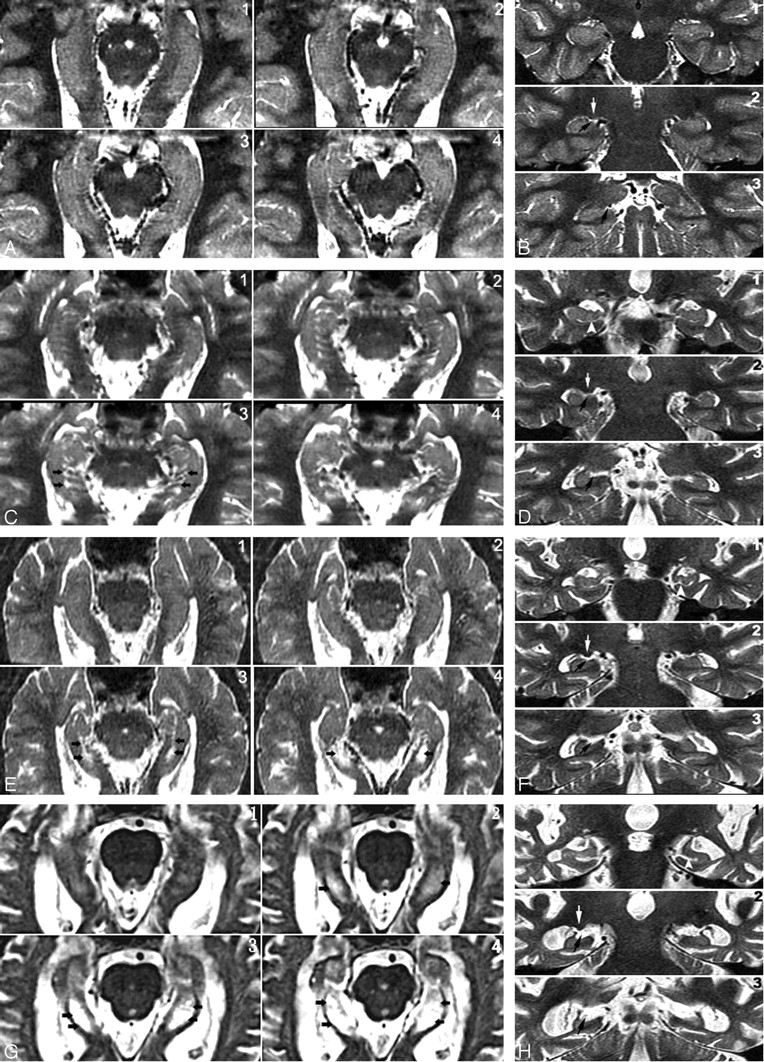

Four-point subjective rating scale of the perihippocampal fissures (PHF).

A and B, Axial and coronal view of same case. Left = 0; right = 0

C and D, Axial and coronal view of same case. Left = 1; right = 1

E and F, Axial and coronal view of same case. Left = 2; right = 2

G and H, Axial and coronal view of same case. Left = 3; right = 3

Axial images were reformatted in 1-mm thickness from inferior to superior, paralleling to the long axial of hippocampus. Black arrows highlight the PHF. There are 3 coronal views for each case showing the head, bodyi and tail of hippocampus. Black arrows highlight the PHF. White arrows on coronal plane show lateral geniculate body. Arrowheads on coronal plane show uncal sulcus.